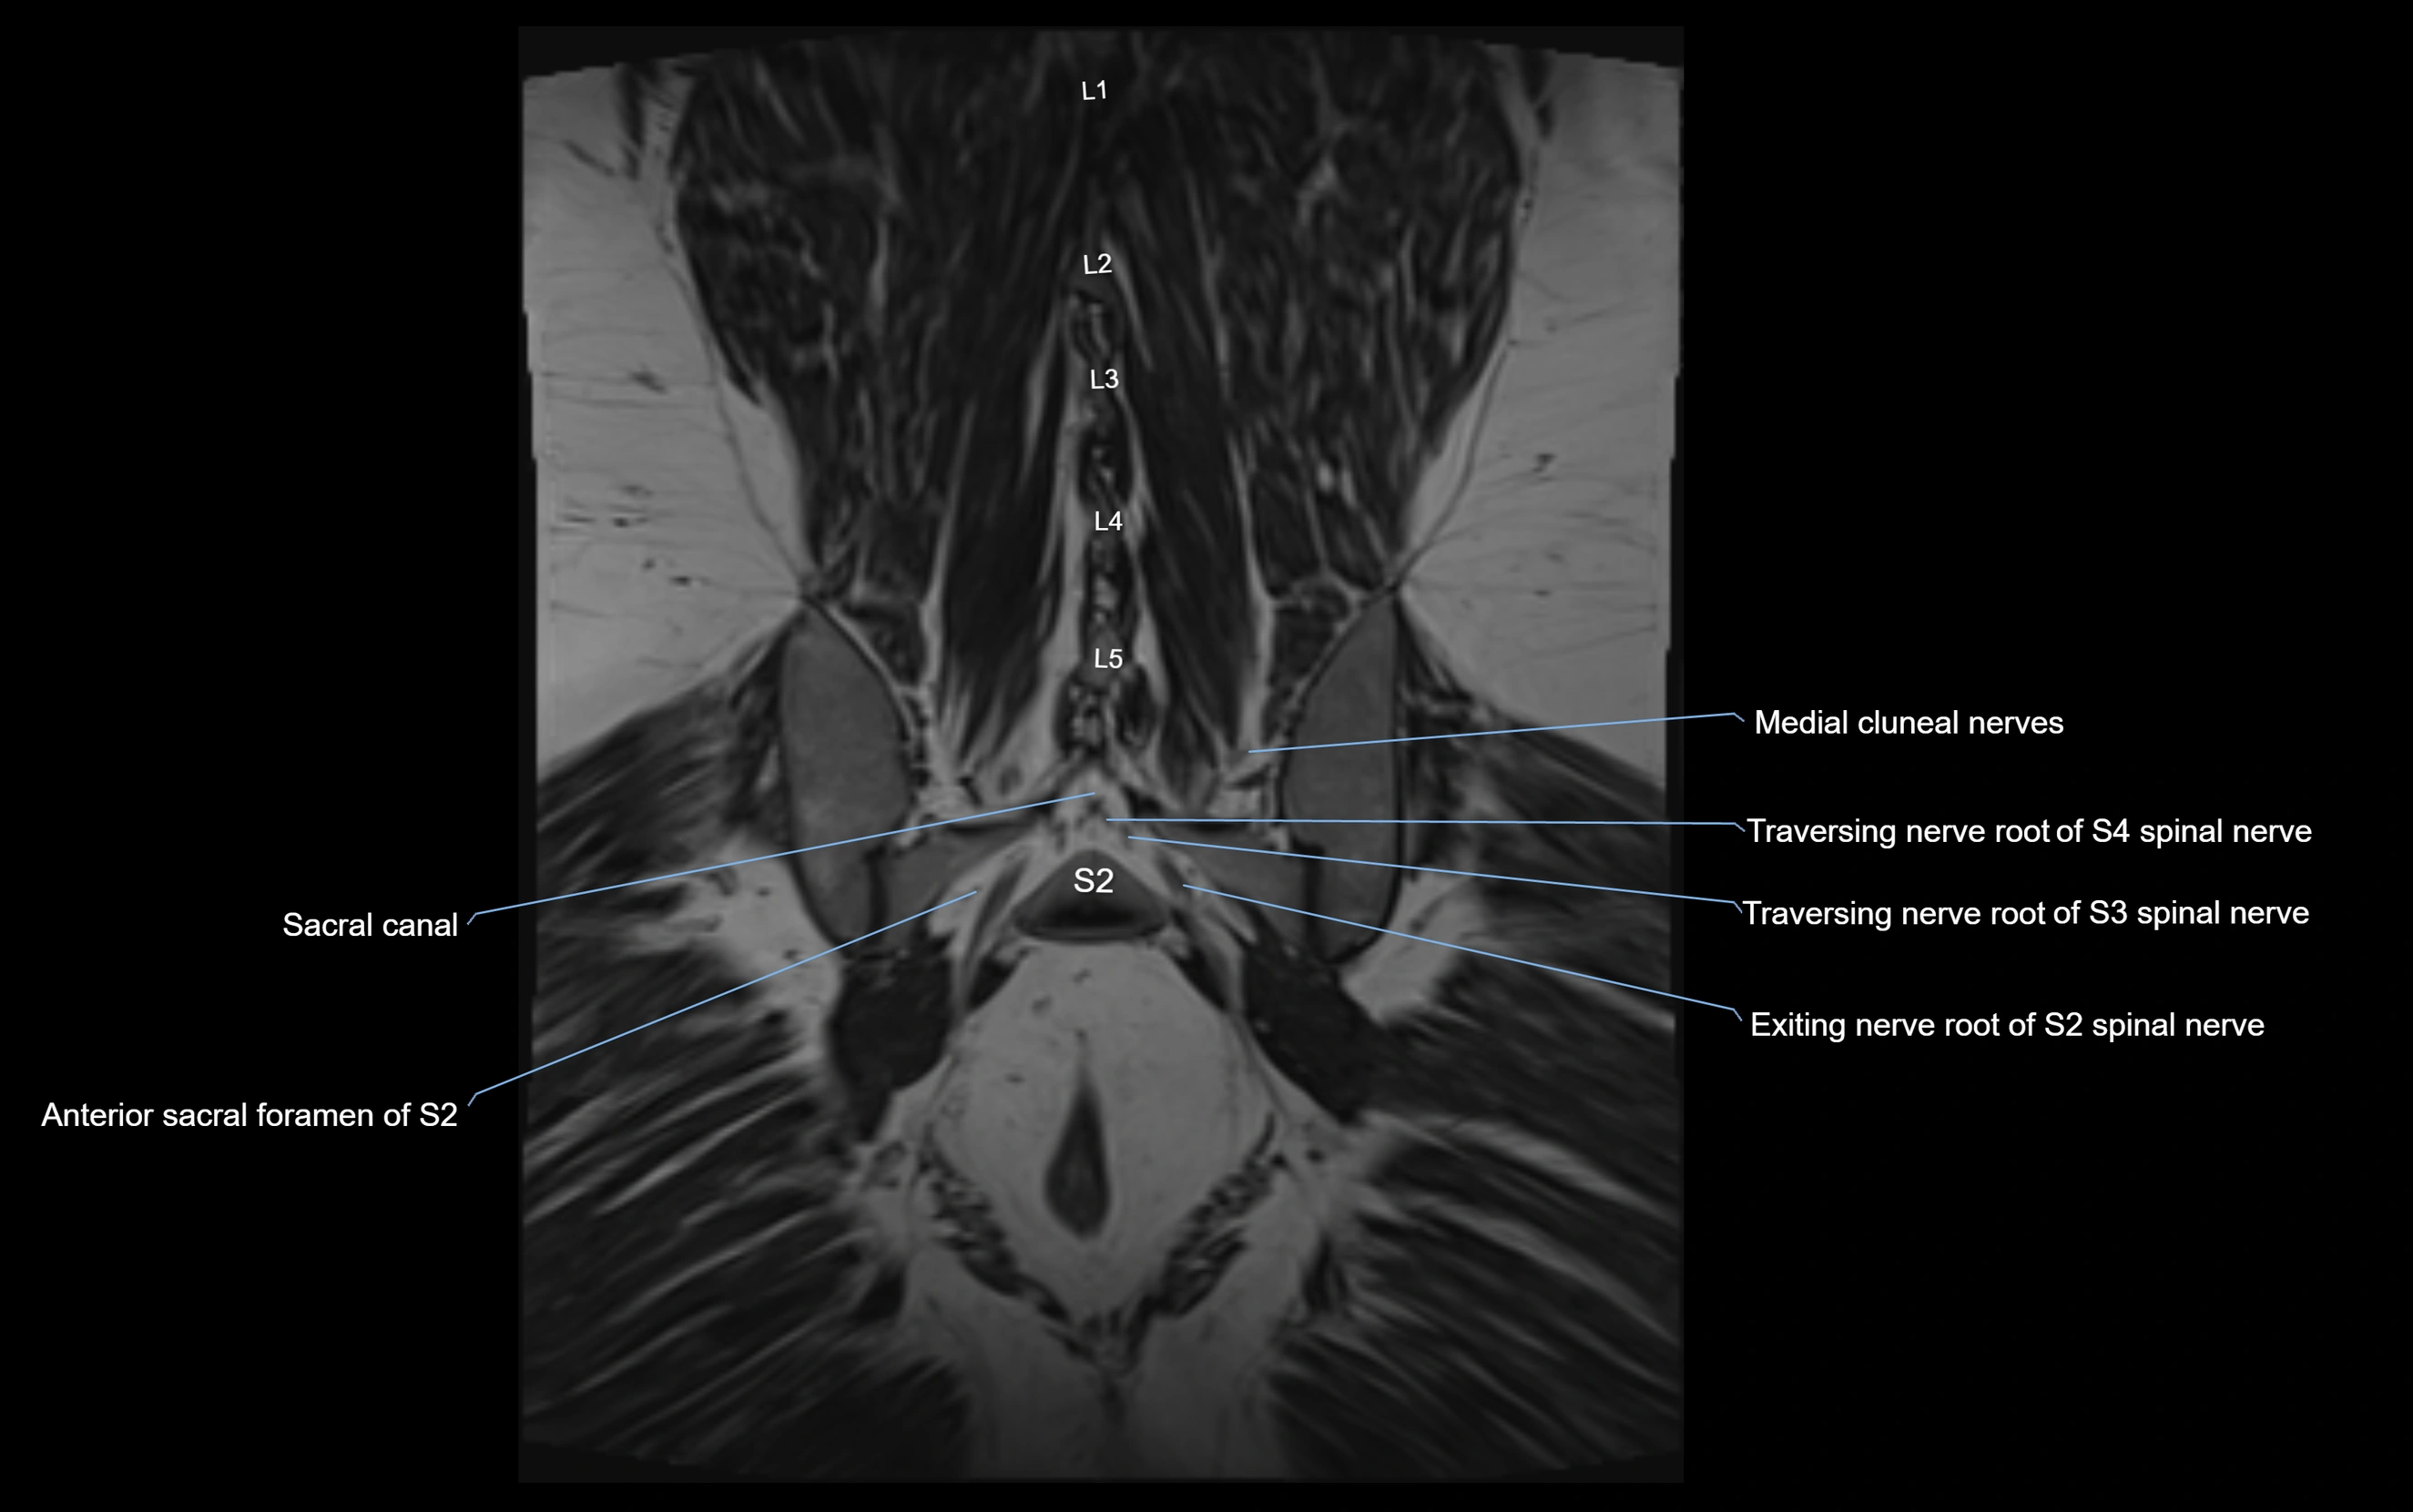

MRI image

image